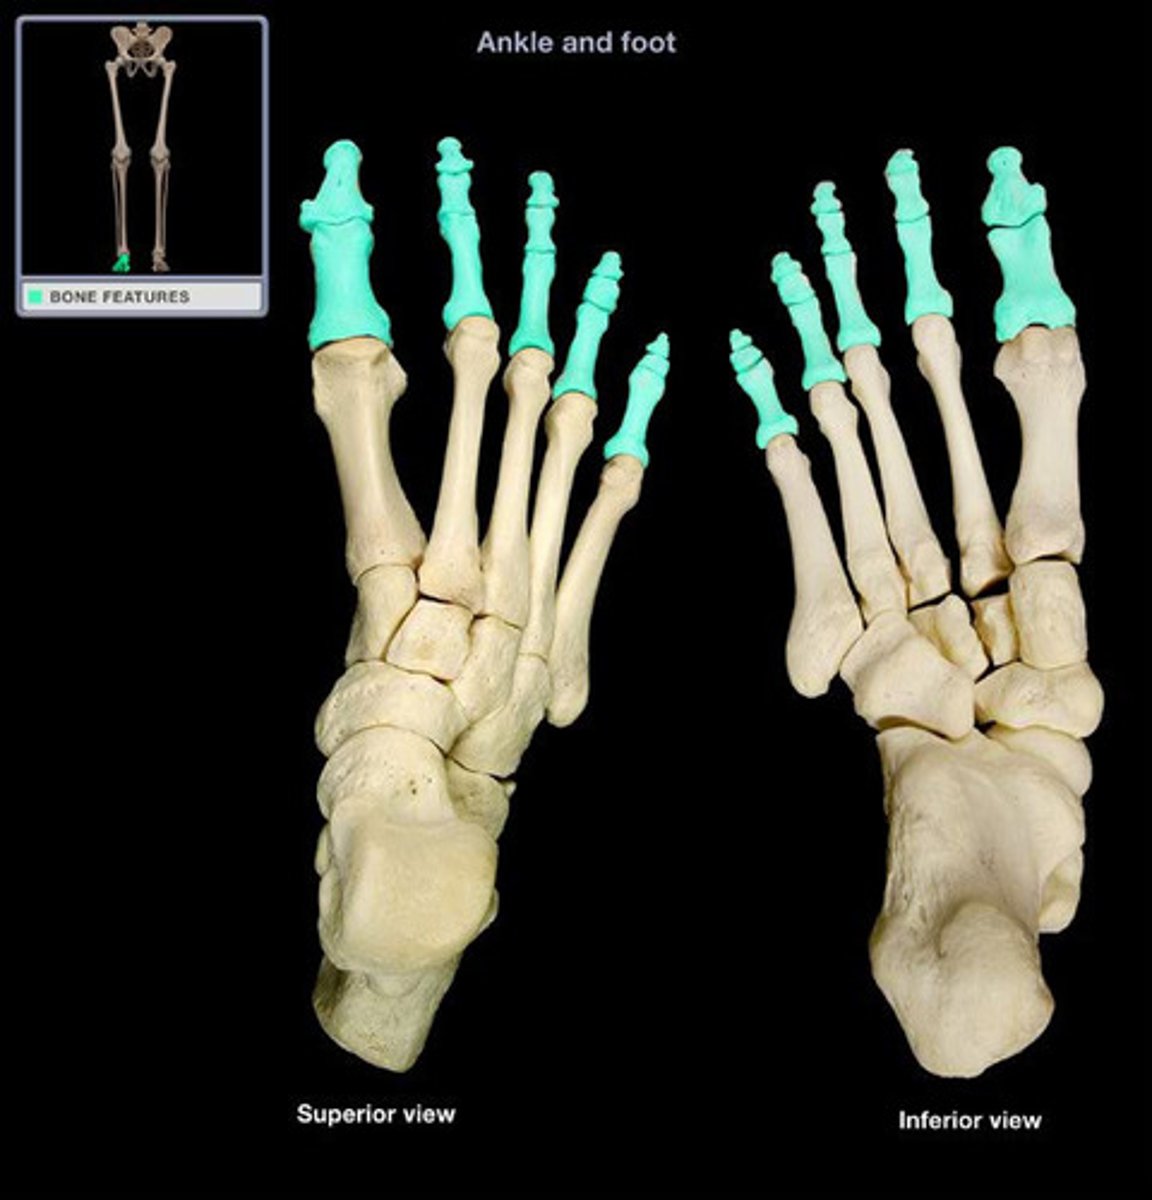

phalanges